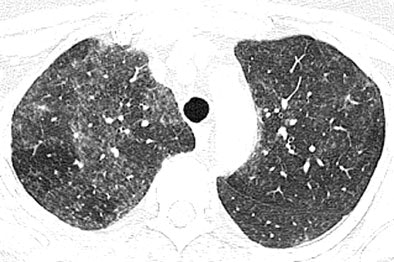

In the new pattern of pulmonary disease known as hot tub lung, "centrilobular nodules and areas of ground-glass attenuation are the most common findings, and typically have diffuse but patchy distribution throughout both lungs," Hartman and colleagues wrote. Expiratory images showed evidence of air trapping in all seven cases for which they were available, they added.

| High-resolution CT images through upper lungs in 53-year-old woman. Above, inspiratory image shows patchy areas of ground-glass attenuation bilaterally with few areas of uninvolved lung. Below, expiratory image shows air trapping in uninvolved areas of upper lungs that is more prominent on right. Images republished with permission of the American Roentgen Ray Society©, from AJR 2007; 188:1050-1053 by Thomas E. Hartmann, Eric Jensen, Henry D. Tazelaar, Viktor Hanak, and Jay H. Ryu. |